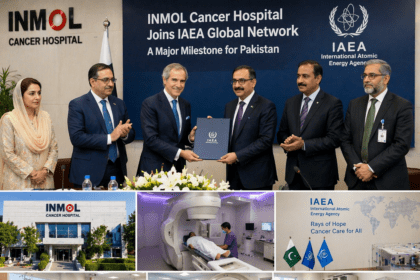

Pakistan’s INMOL Cancer Hospital Joins IAEA Global Network in Major Milestone

Pakistan’s Institute of Nuclear Medicine and Oncology (INMOL) in Lahore has been designated an IAEA…